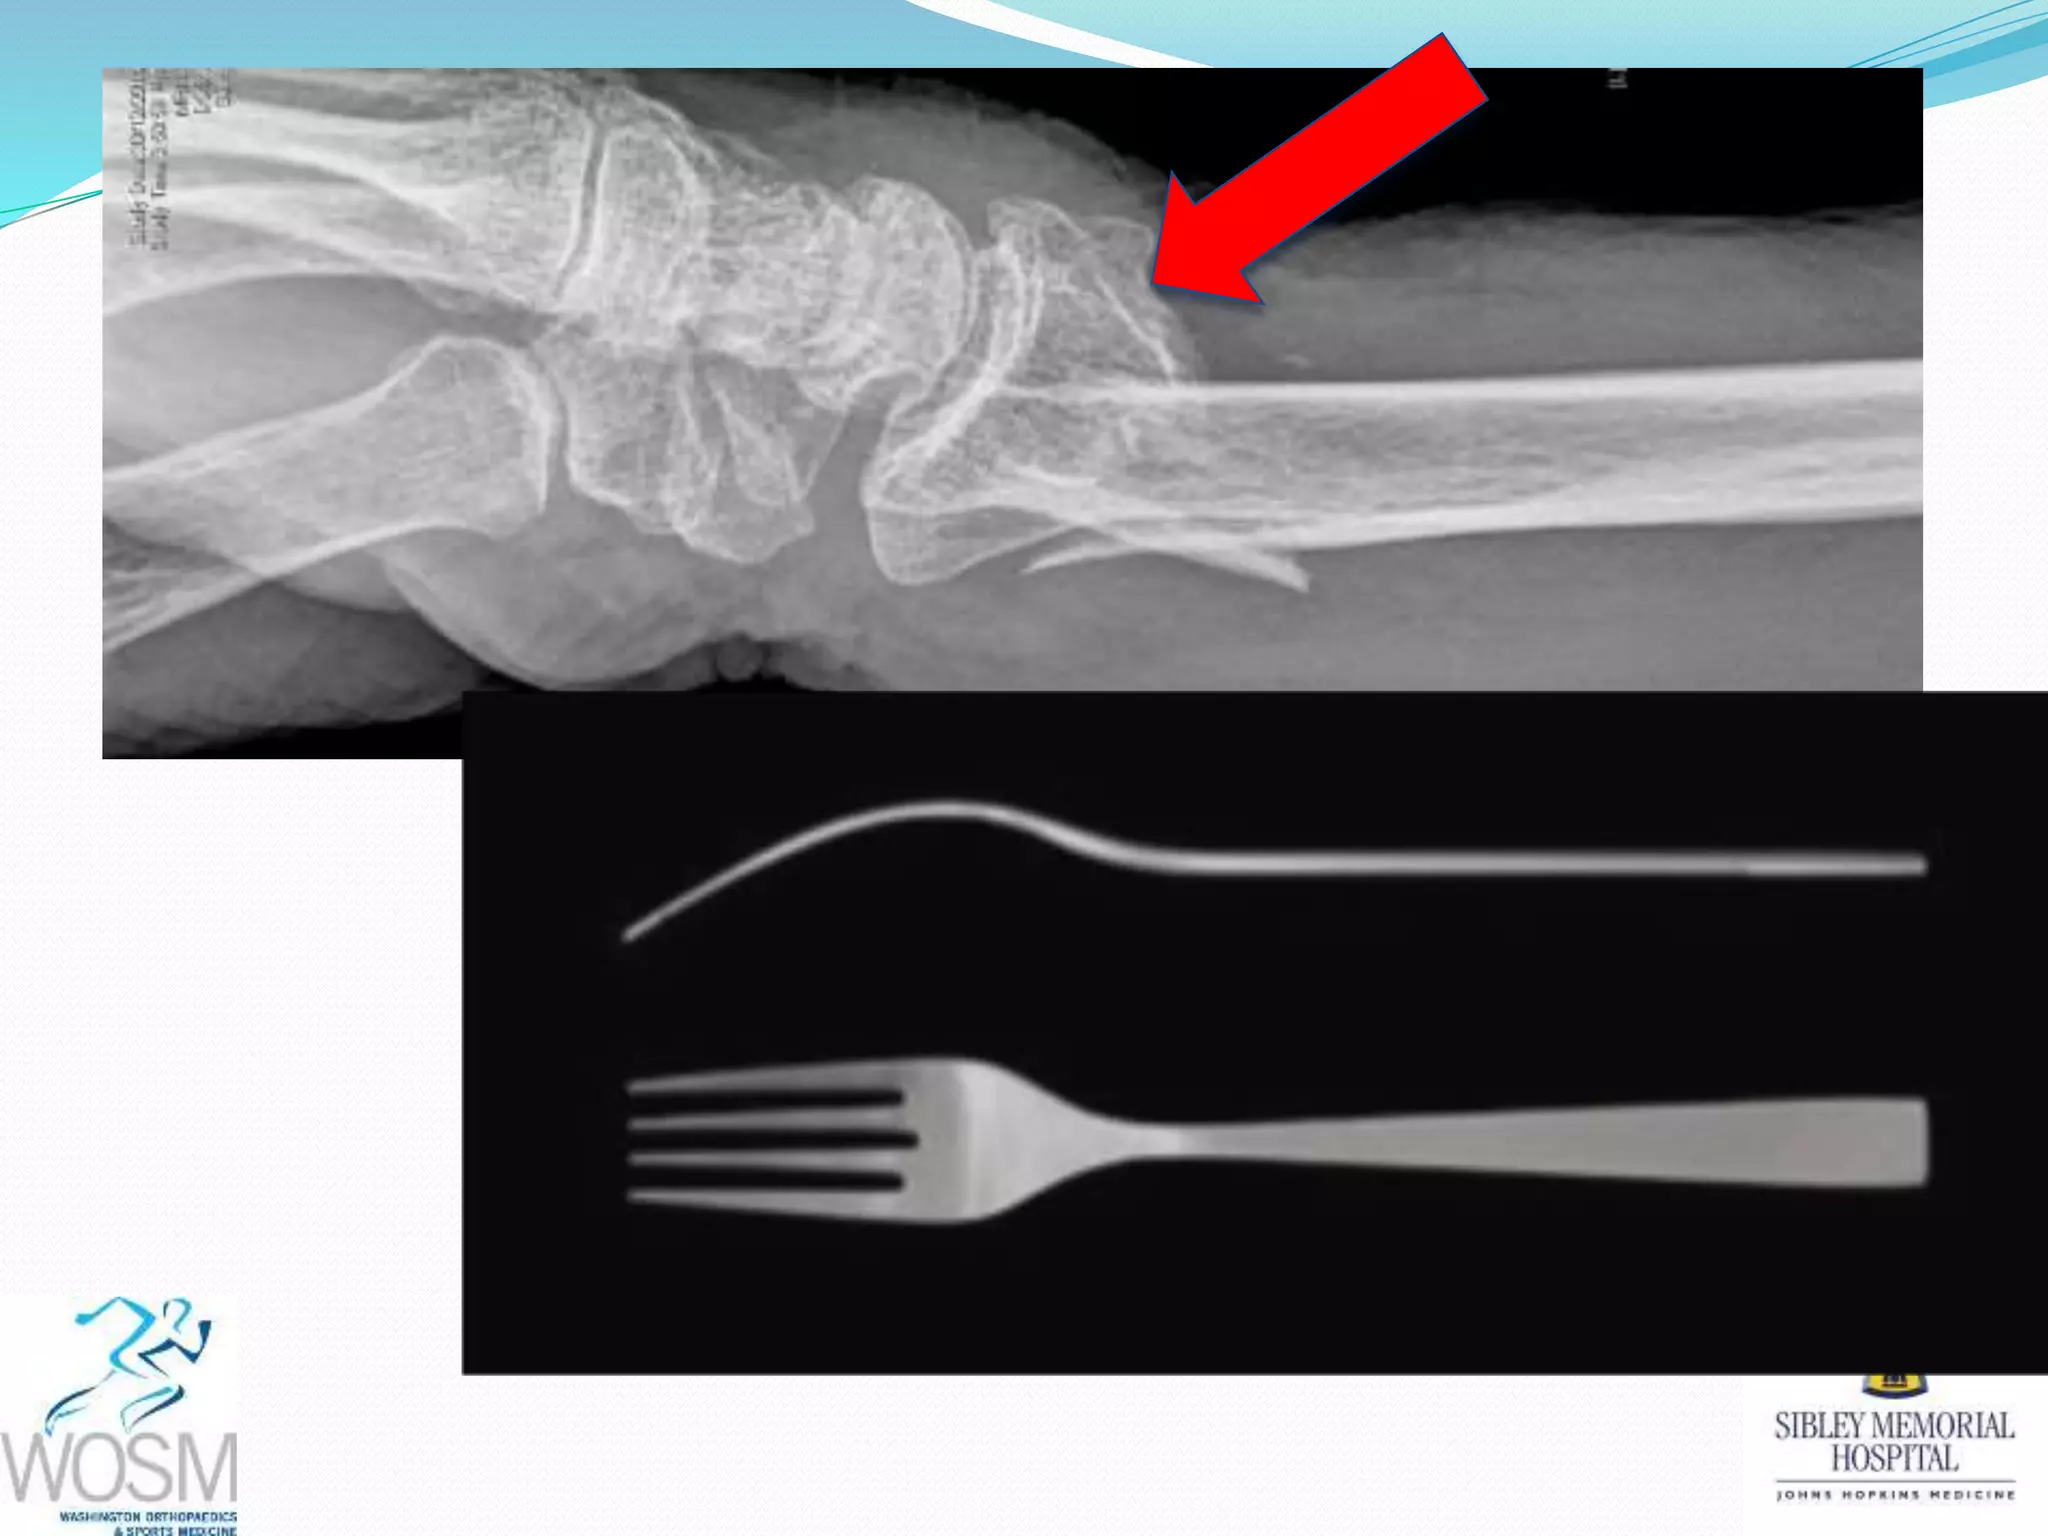

This document discusses wrist fractures, including who is most at risk, common causes, signs and symptoms, treatment options, and prevention. The elderly and those with osteoporosis are most prone to wrist fractures due to falls. Treatment may involve splinting, casting, closed reduction, or surgery depending on the fracture. Maintaining bone health through medication, vitamins, exercise, and diet can help prevent wrist fractures.